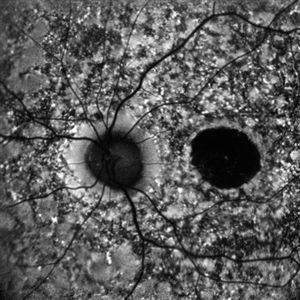

B-FAF in Stargardt's Disease

B-FAF in Stargardt's Disease

Jul 4 2024 by Tejaswita Verma

Blue fundus autofluorescence showing hypoautofluorescence picture of a 28 year old male with 6/60 vision in BE in a case of Stargardt's disease.

Photographer: DR. TEJASWITA VERMA

Imaging device: MIRANTE

Condition/keywords: fundus autofluorescence (FAF), hereditary macular dystrophy, Stargardt disease